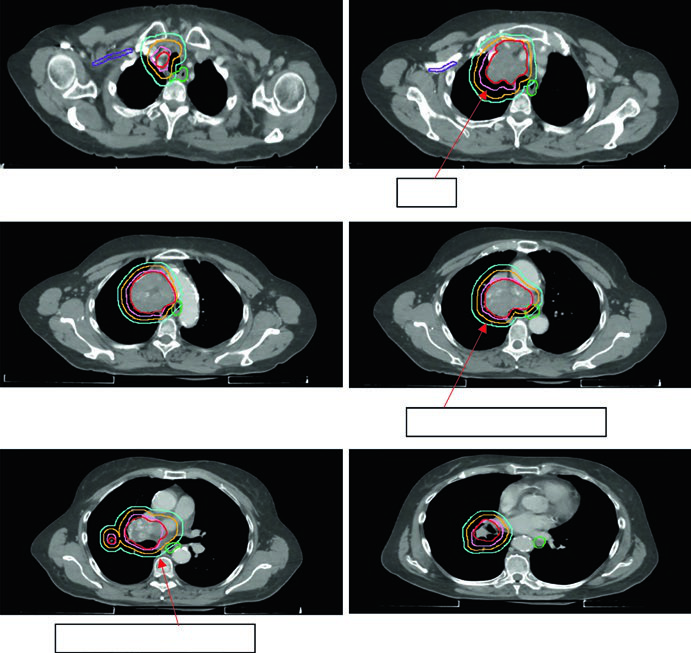

A dose máxima em ponto da PBT é restrita a 55 Gy em qualquer esquema. A Figura 13.2 do texto mostra três casos de estádio inicial: tumor periférico clássico tratado com 54 Gy/3fx, tumor próximo à PBT com 48 Gy/4fx e tumor central com 50 Gy/5fx.

A Figura 13.3 do texto ilustra um caso cT1cN3M0 IIIB: tumor no LSD com linfonodo hilar direito, subcarinal, paratraqueal e SCV direita acometidos. O plano de 60 Gy/30fx cobre todos os sítios PET-positivos com exclusão das cadeias eletivas contralaterais. A Figura 13.4 mostra um caso cT4N3M0 IIIC com SCV bilateral comprometida e síndrome de veia cava superior, exigindo campo que inclui mediastino superior bilateral.

A Figura 13.5 do capítulo mostra um tumor de 5,8 cm no LSE com positividade nos níveis 5 e 10L. O campo limitado conforme Lung ART é o utilizado, com 54 Gy/30fx.

A Figura 13.6 mostra um caso cT2N2 de estádio limitado com o campo envolvido cobrindo tumor primário e linfonodos mediastinais comprometidos, mas excluindo cadeias eletivas. O esquema utilizado foi 45 Gy/30fx BID.

O replanejamento adaptativo deve ser considerado quando a CBCT mostra mudança anatômica significativa — expansão pulmonar ipsilateral, redução de derrame ou colapso em resolução. O caso da Figura 13.7 ilustra uma lesão metastática tratada com 45 Gy/15fx: a reaer ação pulmonar durante o tratamento exigiu replanejamento para proteger o pulmão recém-arejado.